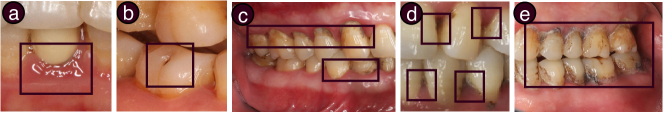

Figure 2: Oral cavity images that contain oral conditions of: (a) periodontal disease, (b) caries, (c) soft deposit, (d) dental calculus, and (e) dental discoloration. Typical areas of the conditions are highlighted with black boxes.

To set the scenario, we provide a brief overview of the five oral conditions for which OralCam supports a user to perform self-examination. We have collaborated with three dental experts to identify these five conditions, all of which are (i)  common in the general population yet often easily ignored, (ii)  vital not just to dental but the overall health of the entire body, and (iii)  visually diagnosable using images of one’s oral cavity. Typical appearance of the five conditions is shown in Figure 2, highlighted with black boxes.

Our detection model should output: (i)  image-wise confidence values for oral conditions’ existence, and (ii)  locations of the existing conditions. As such, we formulate the object localization task [11, 8] for periodontal disease, caries, and dental calculus, which outputs object bounding boxes that can be directly used for locations. We then determine the image-wise confidence of a condition existing with the highest confidence value of all boxes. However, for soft deposit and dental discoloration, the findings usually spread over the whole oral cavity [5, 24], which can be clearly seen on Figure 2(c, e). Thus, formulating these two conditions as localization can be problematic, and leads to heavy workload of data annotating for supervised training. As a result, we formulate image classification tasks [19, 7] for soft deposit and dental discoloration, while their regions of interest are reasoned as heatmaps based on model attention, which will be described in a following subsection.